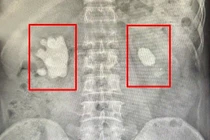

Qua thăm khám lâm sàng và xét nghiệm hình ảnh, bé được chẩn đoán sỏi khúc nối bể thận - niệu quản phải, kích thước lên tới 20mm, kèm biến chứng thận phải ứ nước độ II.

soi-tre-2.jpg

Sức khỏe của bệnh nhi H. ổn định hoàn toàn và được xuất viện chỉ sau 5 ngày được phẫu thuật tán sỏi thận qua da đường hầm siêu nhỏ - Ảnh BVCC